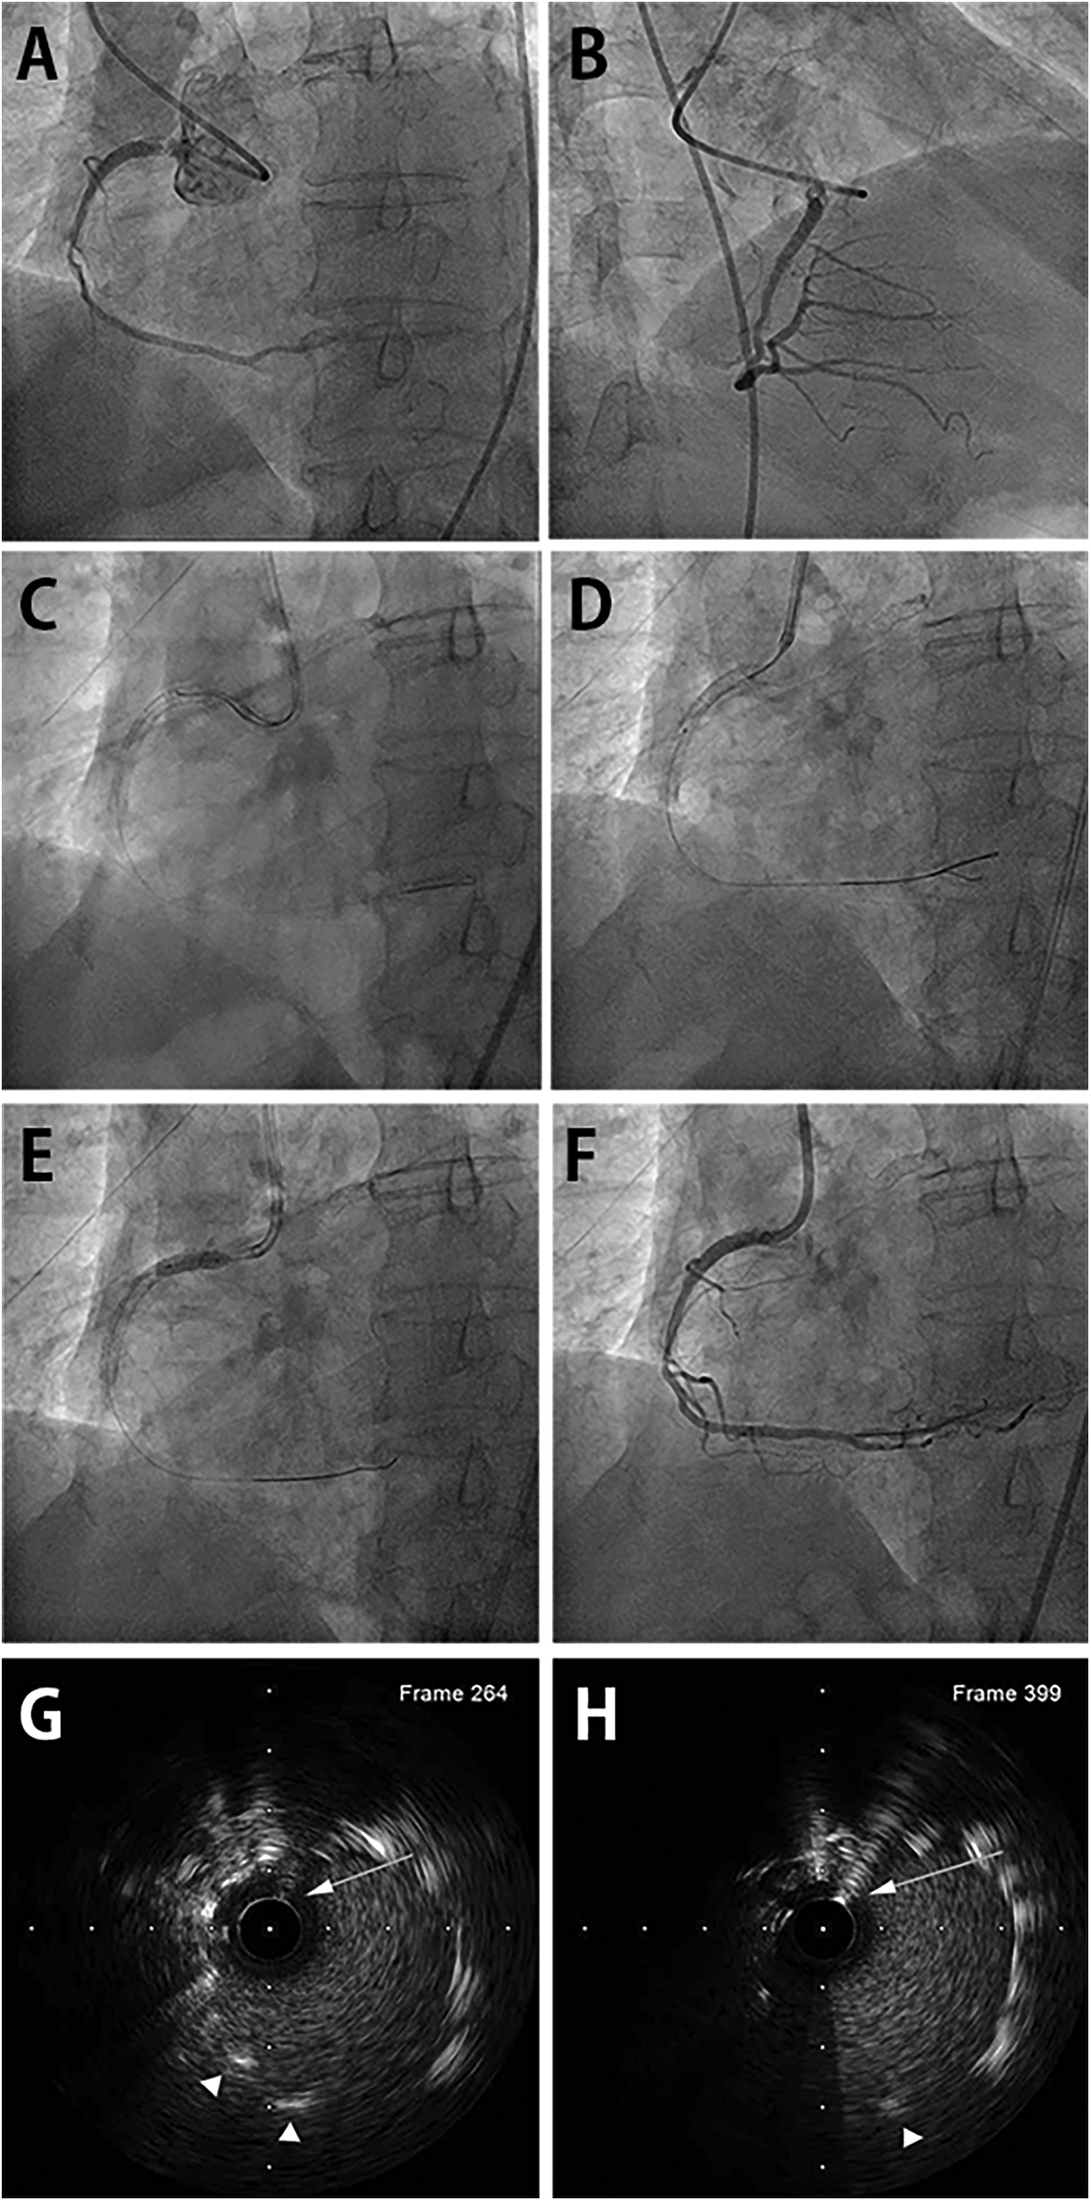

Figure 1

DLC-facilitated aorto-ostial wiring technique in the RCA. (A) Coronary angiography from the left anterior oblique view shows in-stent restenosis of the previously placed aorto-ostial RCA stent. (B) Non-selective angiography from the right anterior oblique view also reveals the in-stent restenosis, alluding challenging cannulation. (C) The first wire is inserted in the RCA through the stent-side strut. The second wire successfully enters the central stent lumen facilitated by DLC. (D) The wire's central position is confirmed using an intravascular ultrasound catheter. (E) The drug-eluting balloon is inflated after proper lesion preparation. (F) Final coronary angiography shows a good angiographic result with coaxially engaged guiding catheter. (G) IVUS image revealing luminal position of the second wire in the mid portion of the protruding stent outside the coronary artery. First wire was retracted before IVUS imaging. (H) IVUS image showing luminal position at the very proximal end of the protruding stent. DLC, dual-lumen microcatheter; RCA, right coronary artery; IVUS, intravascular ultrasound. (Arrows indicate second wire. Arrowheads indicate stent strut.)